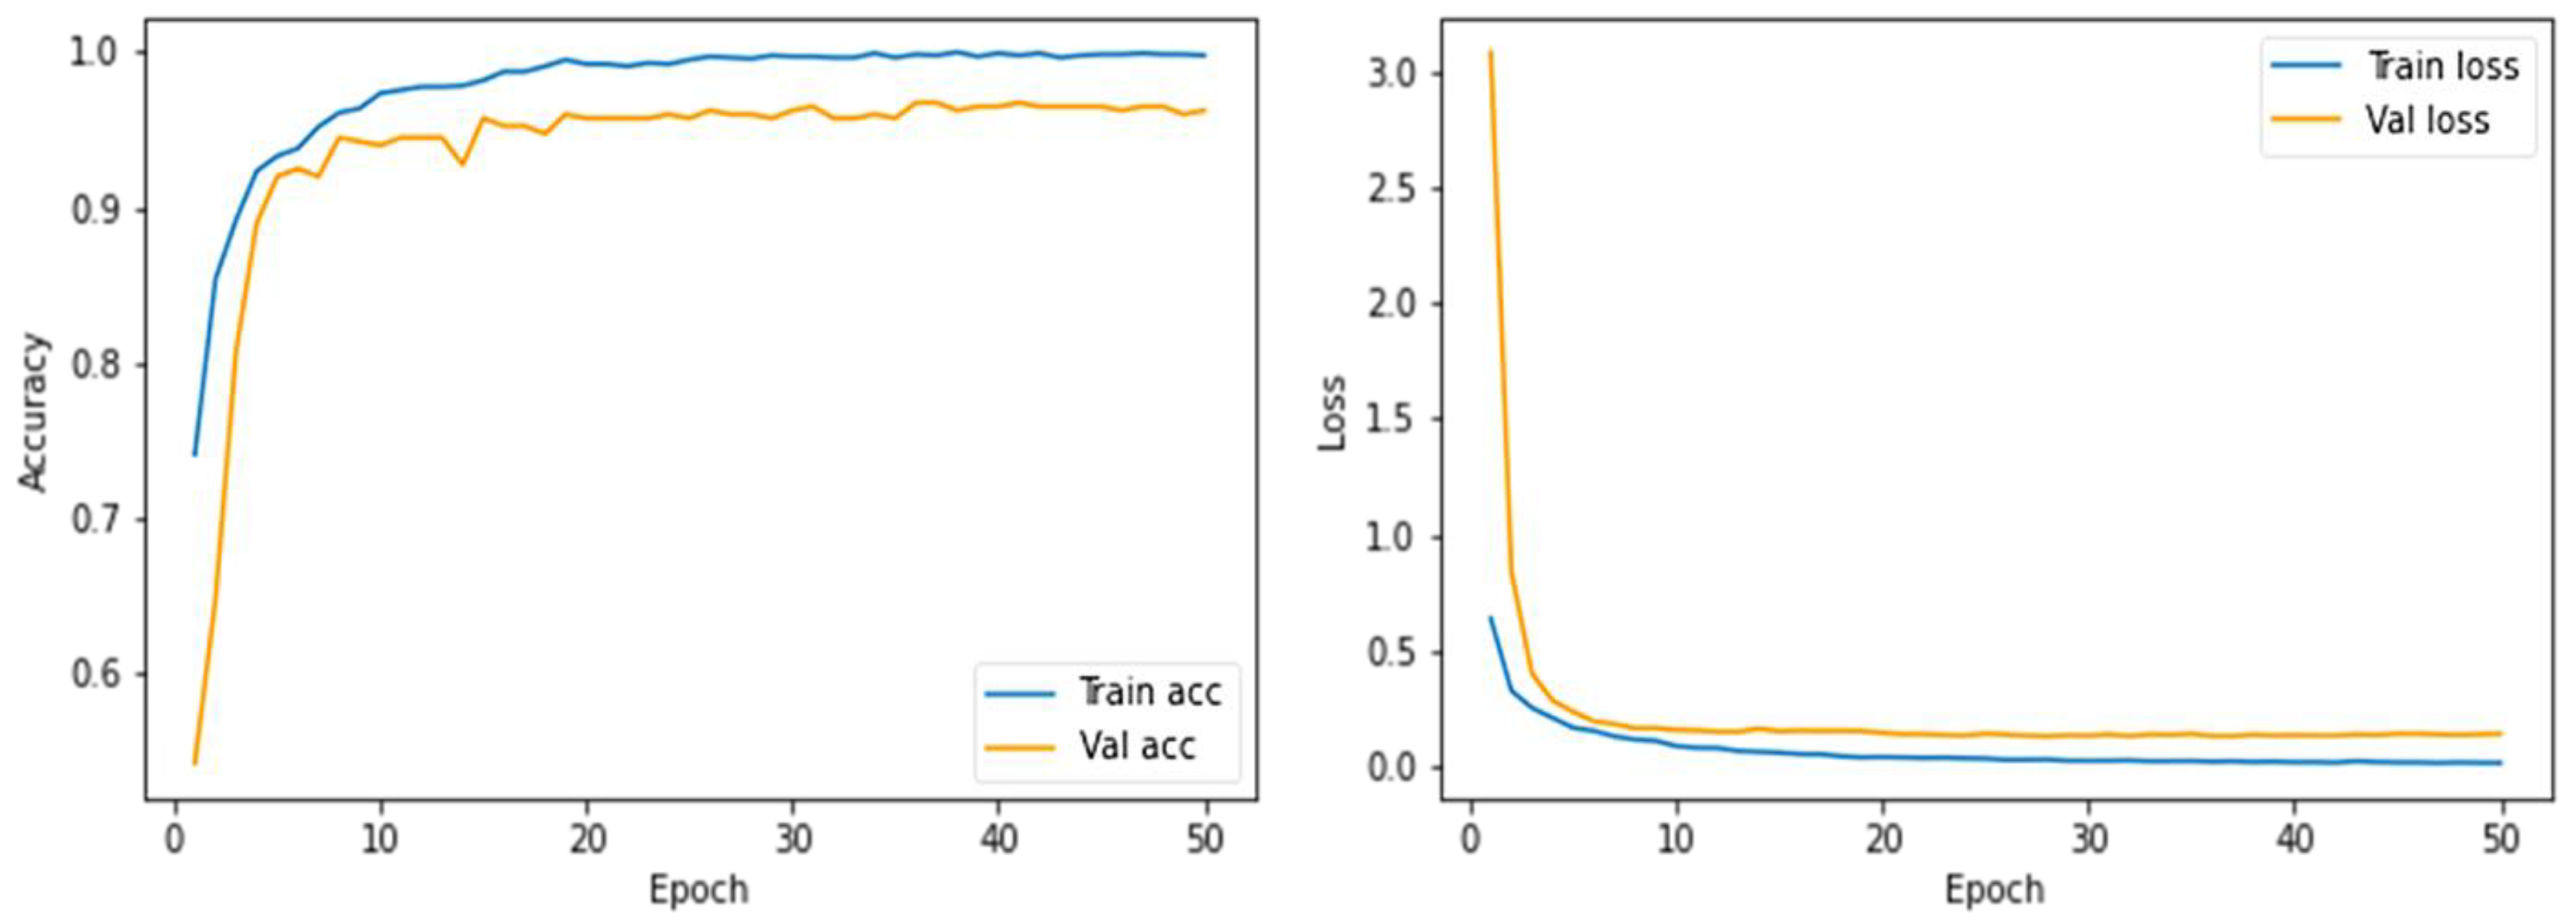

4.1. Training Details

4.3. Results Evaluation Using BraTS 2018 Dataset

4.4. Results Evaluation Using Figshare Dataset